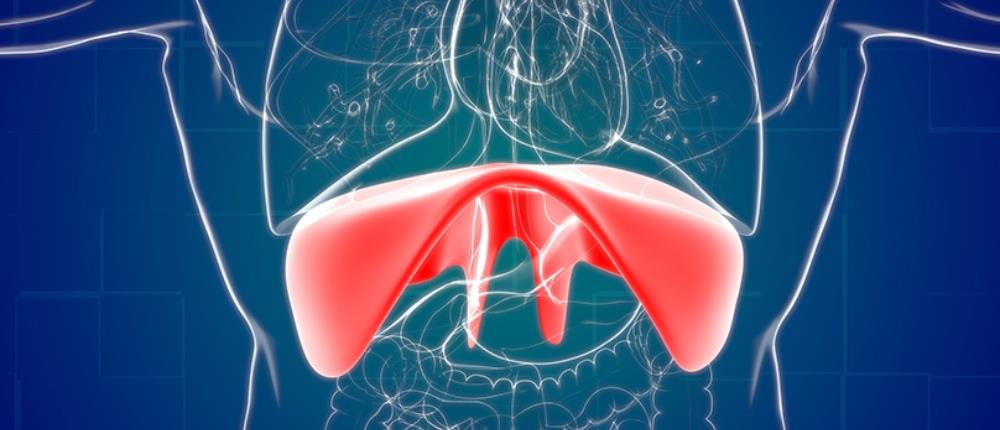

Η διαφραγματοκήλη διαφέρει από τις υπόλοιπες κήλες της κοιλιακής χώρας λόγω του ότι εμφανίζεται στο εσωτερικό της κοιλιάς. Πιο συγκεκριμένα, η διαφραγματοκήλη προκύπτει όταν δημιουργείται ένα κενό/χάσμα στο διάφραγμα, το μυ που χωρίζει την κοιλότητα του θώρακα από την κοιλιακή κοιλότητα, το οποίο επιτρέπει στα ενδοκοιλιακά σπλάχνα (στομάχι, έντερο, ήπαρ) να μετακινηθούν στη θωρακική κοιλότητα, προξενώντας μια σειρά από συμπτώματα και επιπλοκές για τον πάσχοντα.